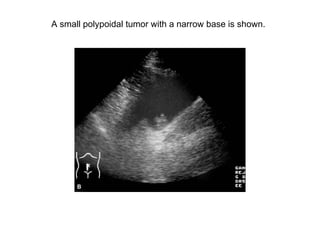

Bladder tumor

A small polypoidal tumor with a narrow base is shown.